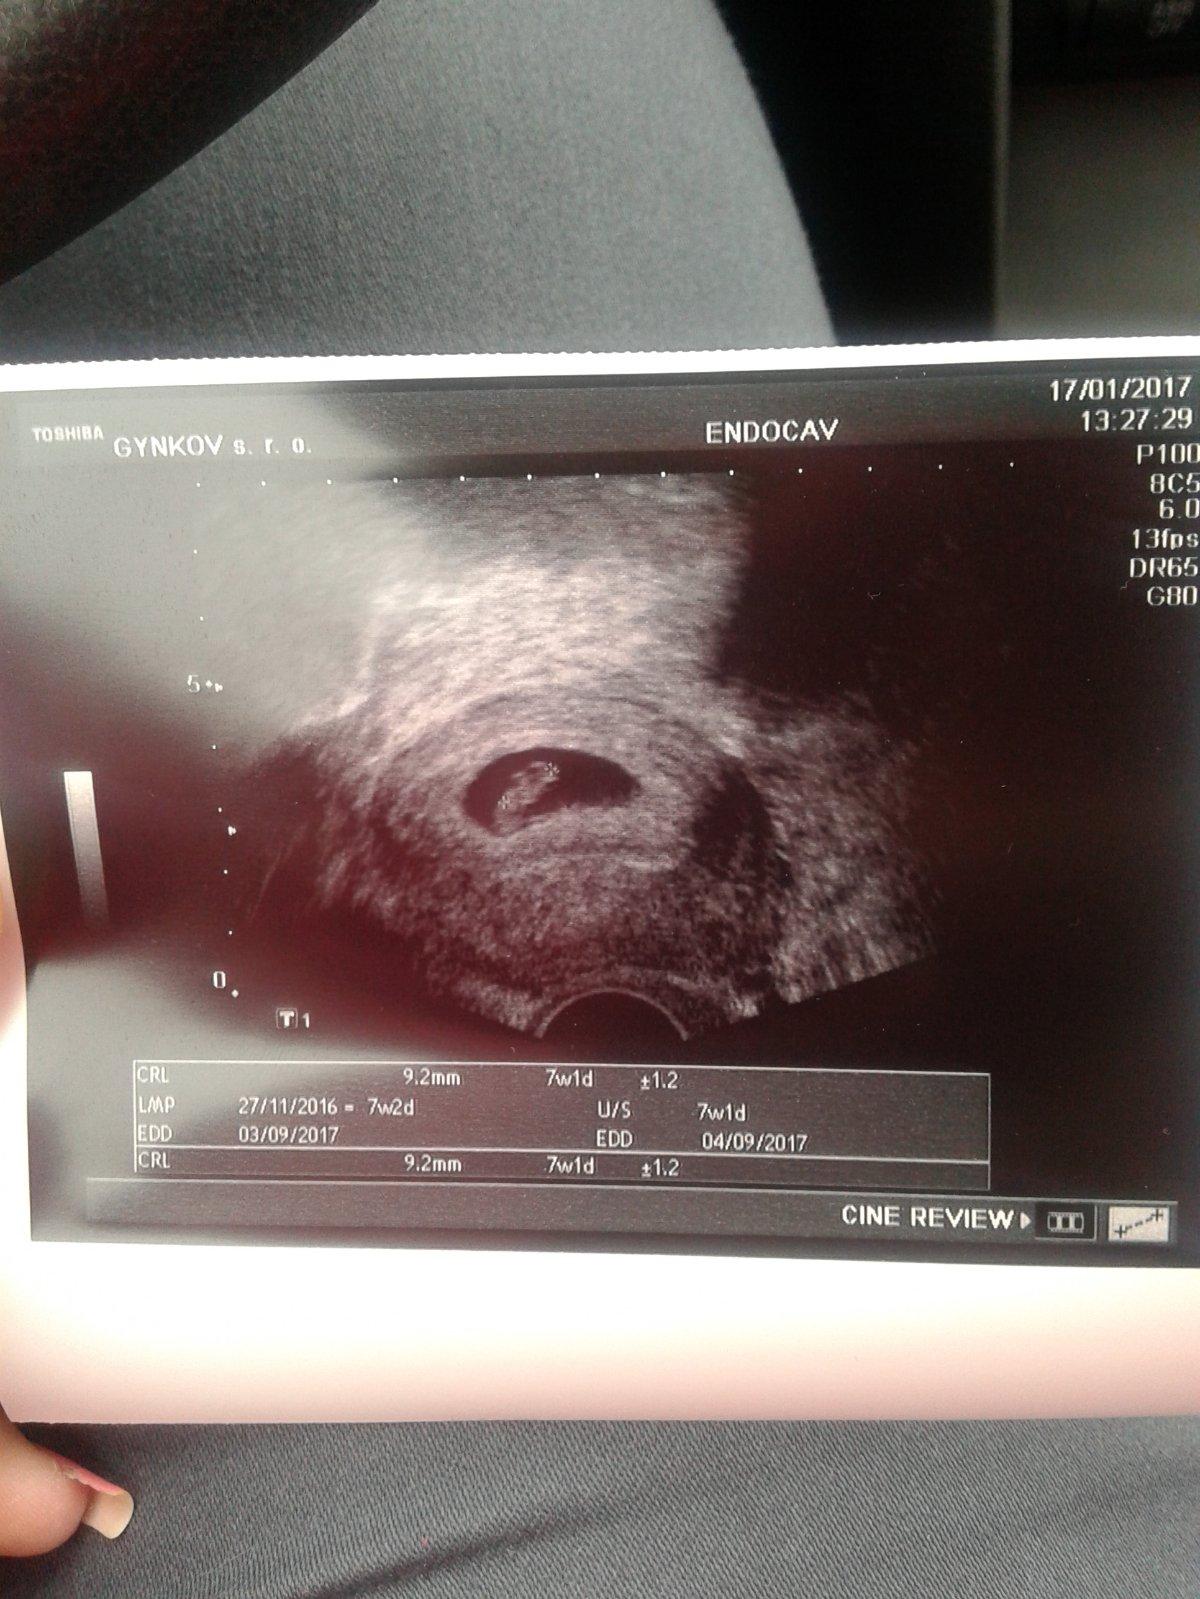

Na prvni fotce 5+2tt (vylouceno mimodelozni a byl videt zloutkovy vacek ) druha fotka 7+2tt uz krasne bilo srdicko 🙂 je pravda, ze zalezi na utz doktora, ale me v tech 5+2tt ani nenapadlo, ze by bylo srdicko, tak budte holky v klidu, do 8tt casu dost 😉

Toto je ma fotka 5+2

Vypada to jako prstynek a jdou videt 2 křizky ze neco měril..

@sukubka je to urcite v poradku, akorat to ma hodne priblizene 🙂

@sukubka je to v pořádku tři já našla na netu je to podobné